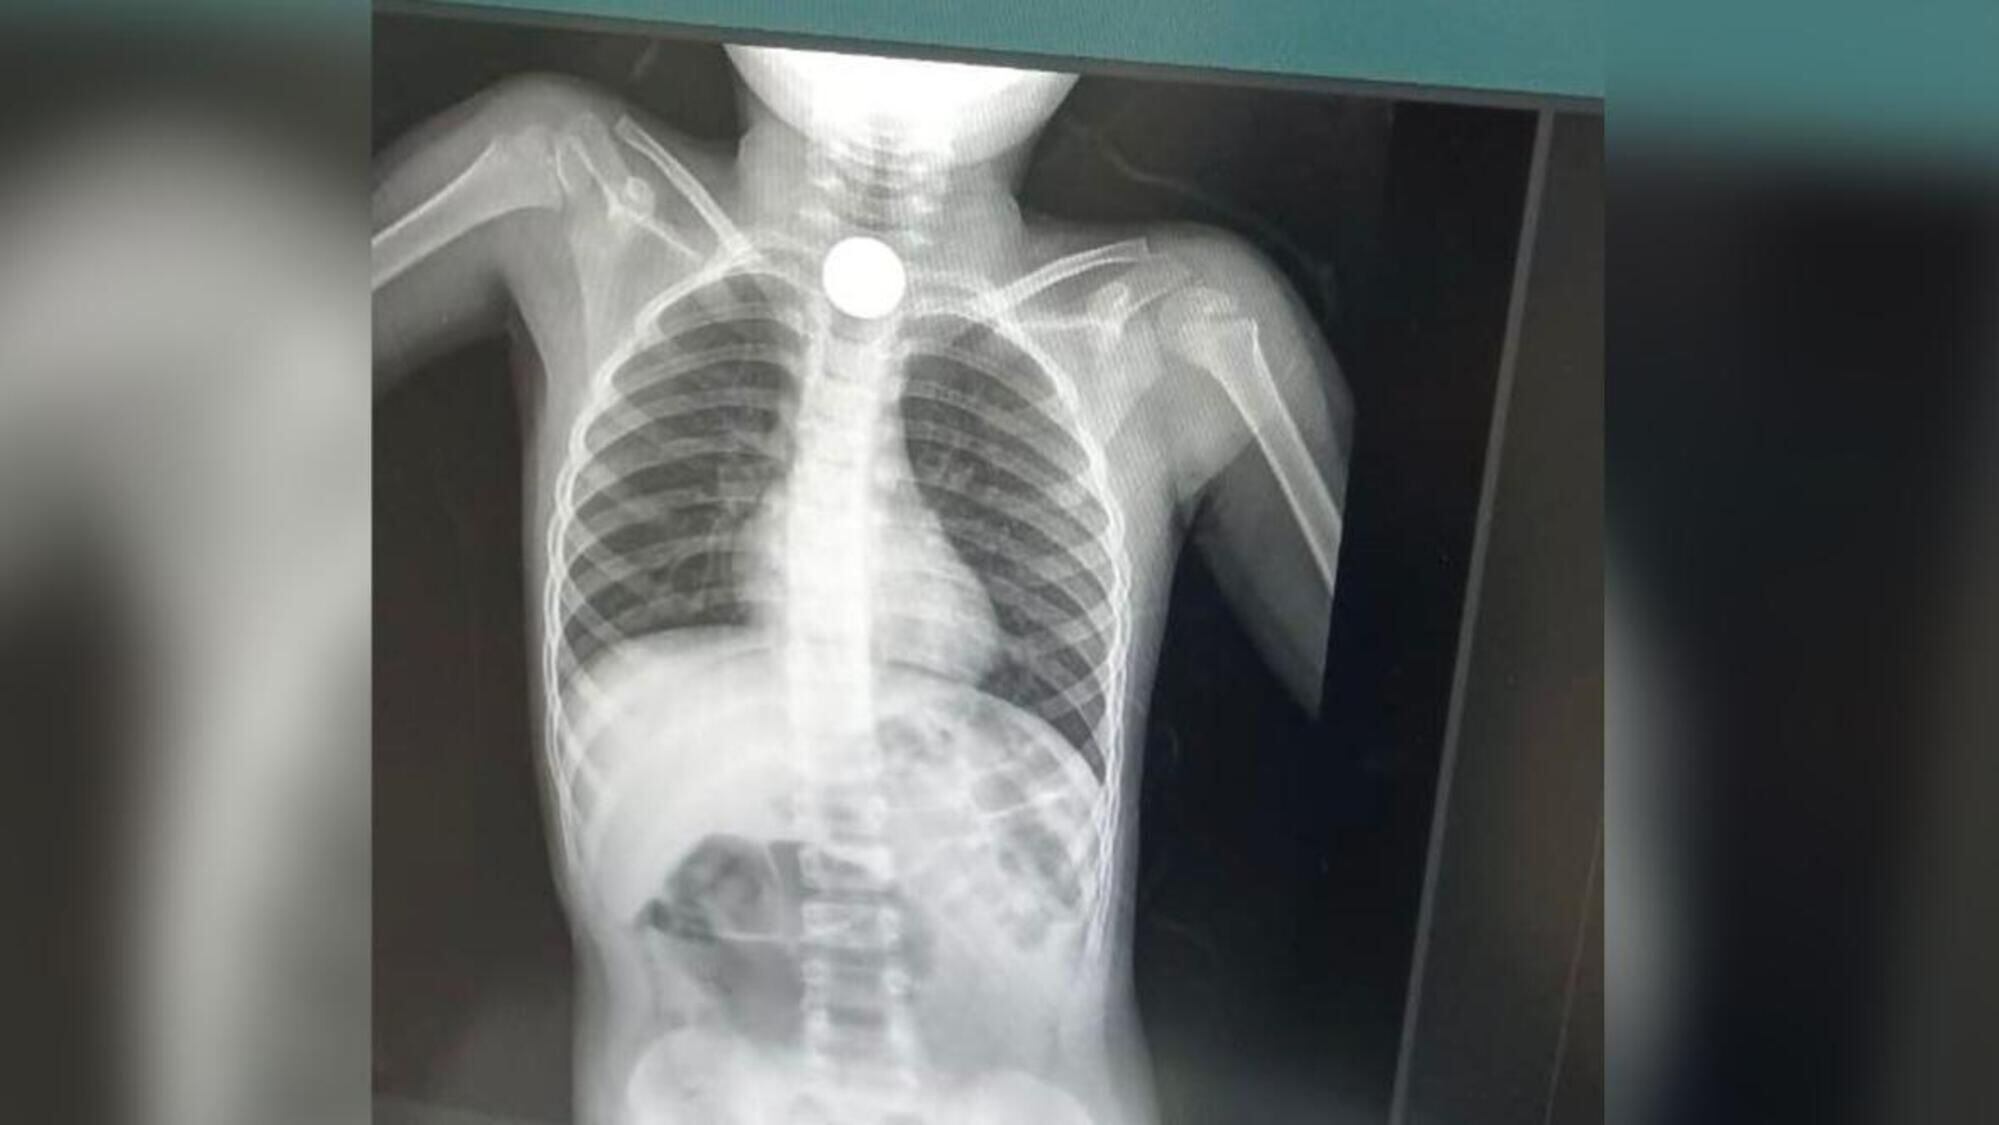

Placa del menor/ Jairo López